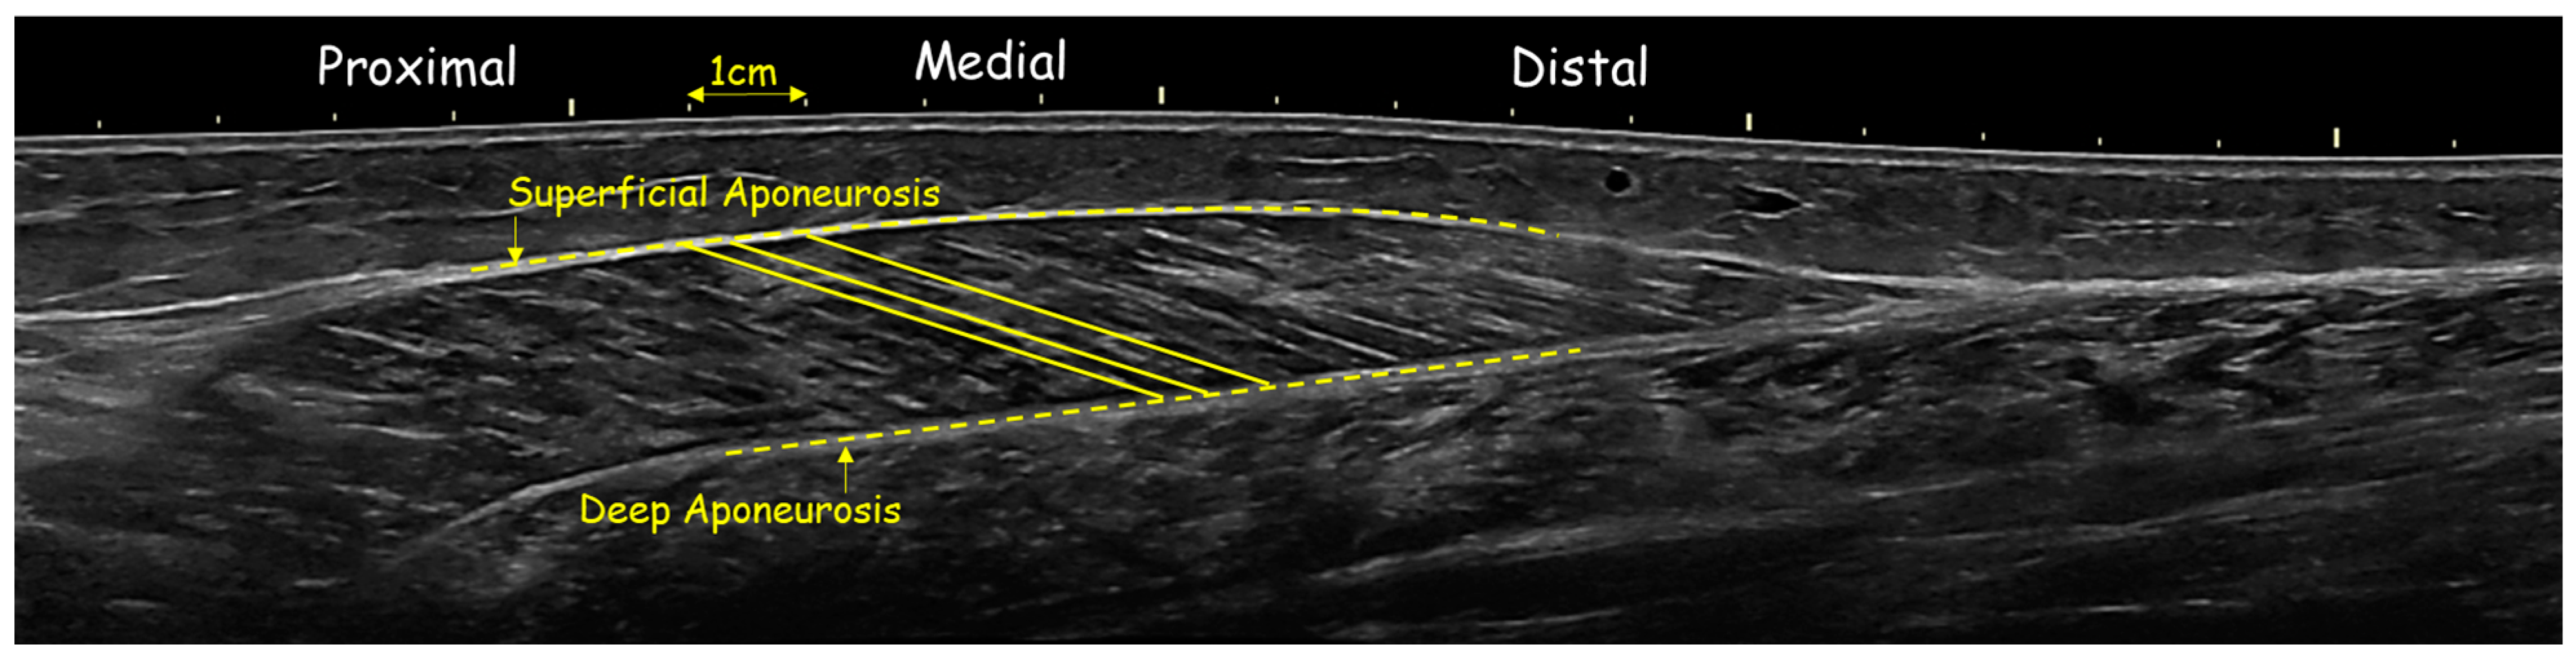

2.4. Ultrasonography